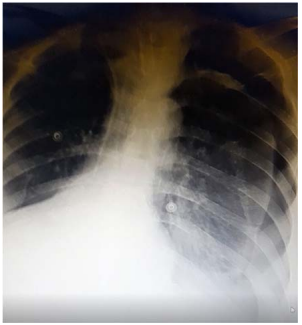

Caso clínico para responder à questão.

Um paciente de 50 anos de idade encontra-se, internado na UTI por conta de choque séptico de foco pulmonar, em ventilação mecânica na modalidade pressão e no modo assisto-controlado. Pela manhã foi submetido a acesso venoso central em veia axilar guiado por ultrassonografia. Ao exame físico, notou-se que o paciente está com hipotensão e taquicardia. A primeira hipótese diagnóstica é pneumotórax e é realizada radiografia com imagem apresentada.